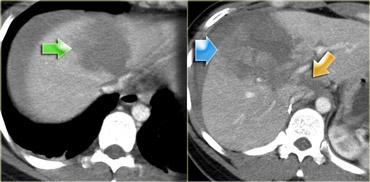

Trước tiên hãy quan sát các hình ảnh bên trái của bệnh nhân bị chấn thương gan.

Mô tả các dấu hiệu hình ảnh.

Sau đó tiếp tục.

Các dấu hiệu bao gồm:

- Mũi tên xanh lá: vùng giảm tỷ trọng hình bầu dục phù hợp với tụ máu

-

Mũi tên vàng: vùng giảm tỷ trọng hình tuyến tính phù hợp với đường rách.

Lưu ý rằng đường rách này đi qua nhánh trái của tĩnh mạch cửa - Mũi tên xanh dương: vùng giảm tỷ trọng mờ, ranh giới không rõ phù hợp với dập gan

- Dịch quanh gan

- Gần như có sự đứt ngang hoàn toàn của gan, nhưng cả hai thùy đều còn ngấm thuốc, cho thấy nguồn cung cấp mạch máu vẫn còn bình thường.